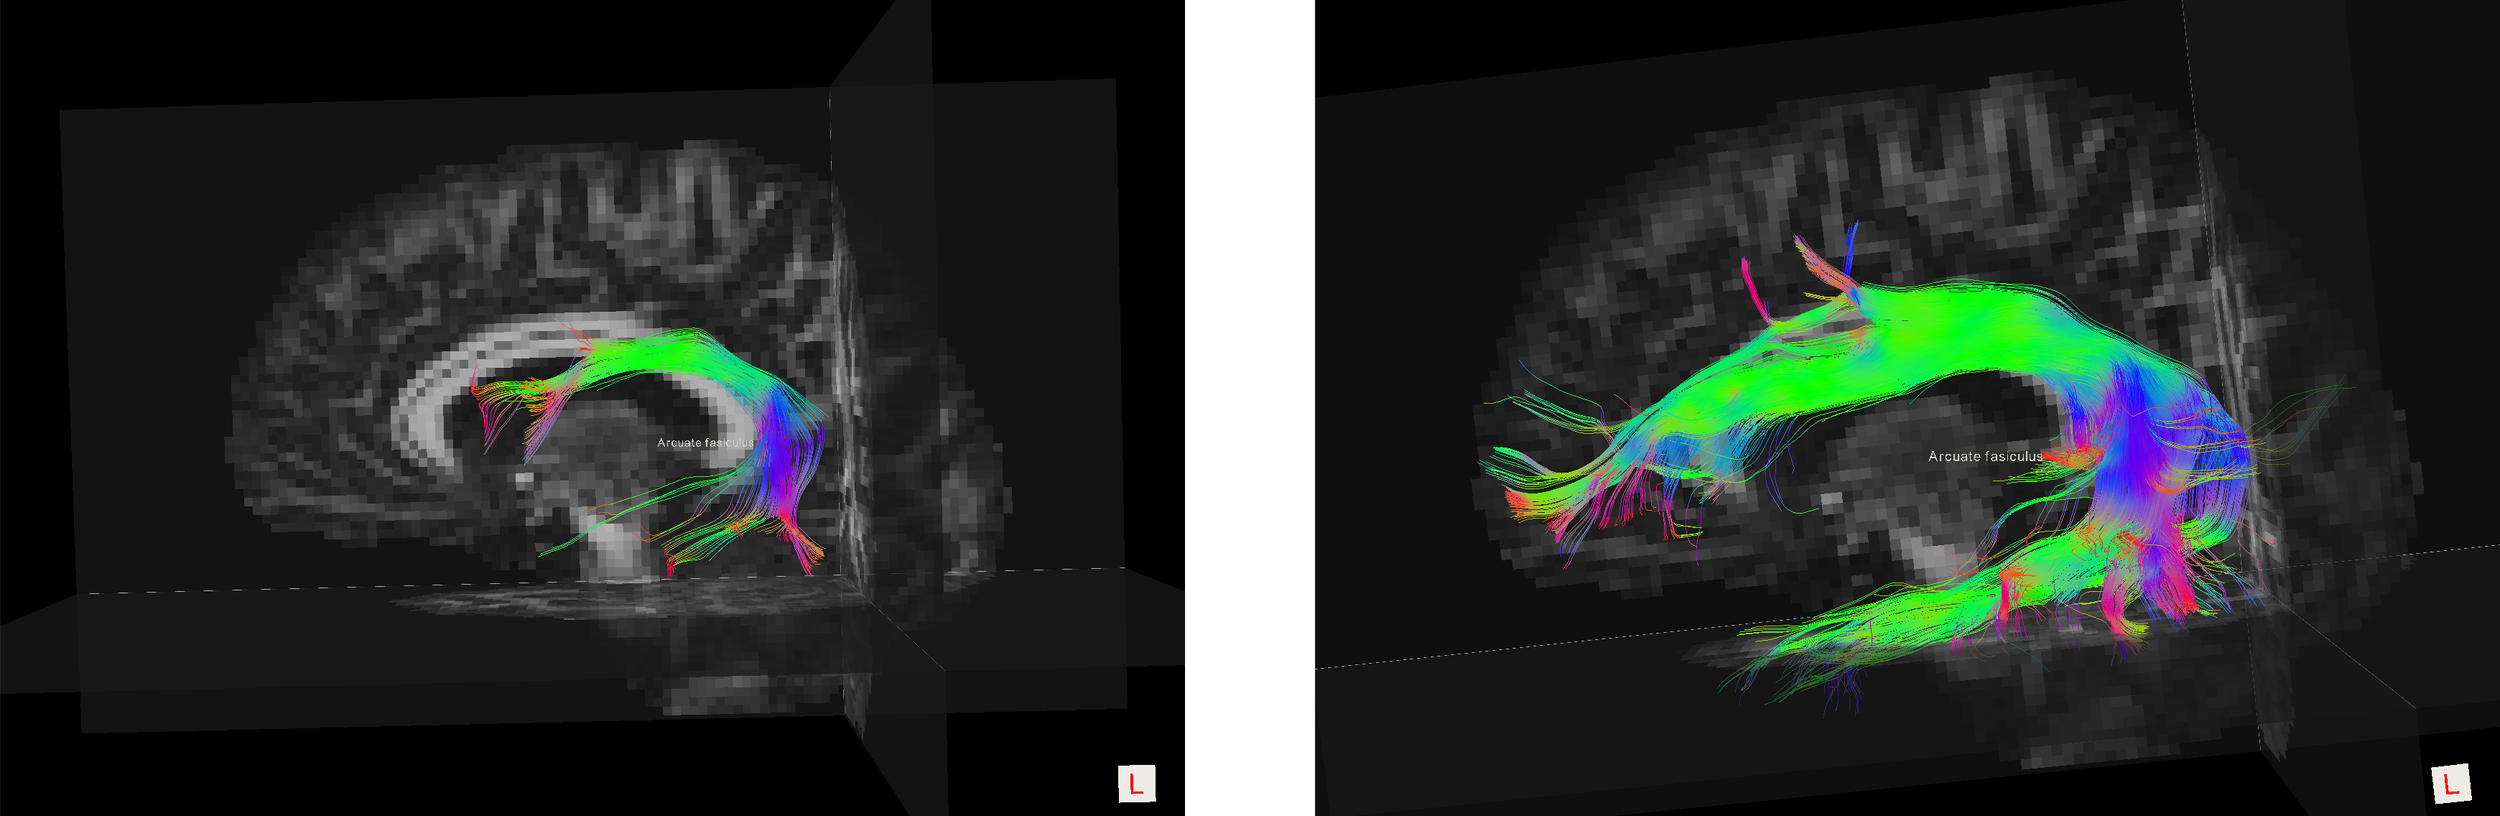

The images below show the corticospinal tract and the arcuate fasciculus from the same scan and patient.

Dissected Arcuate fasiculus tract using DTI and SD